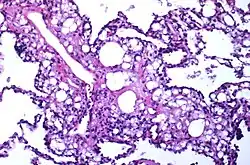

| Numerous interstitial fat globules of varying size accompanied by inflammation and fibrosis is characteristic of chronic lipid pneumonia secondary to lipid aspiration. | |

Once inhaled, these fuels induce an inflammatory reaction in lung tissue. They are not metabolized by tissue enzymes, but undergo emulsification and become engulfed by macrophages which, with time, may disintegrate and release oily substances surrounded by fibrous tissue and giant cells.[8]